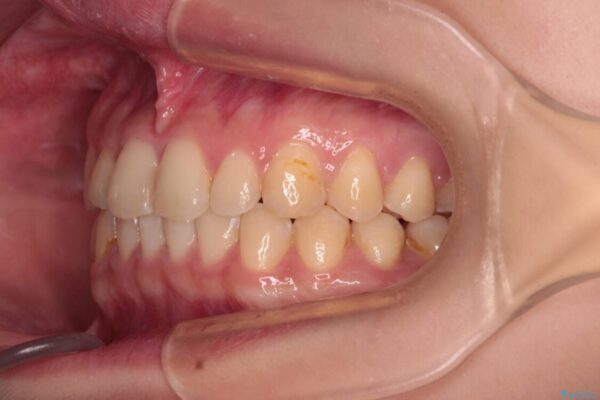

治療前

• 治療途中の奥歯と矯正治療の後戻り インビザライン・ライトによる矯正治療 治療前画像